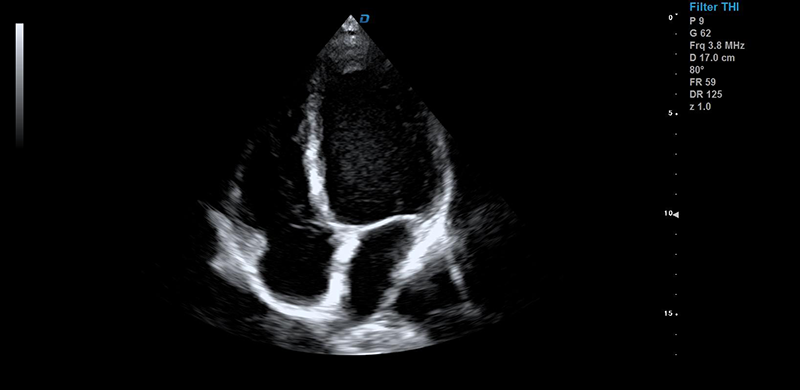

彩超機心臟檢測圖

心臟